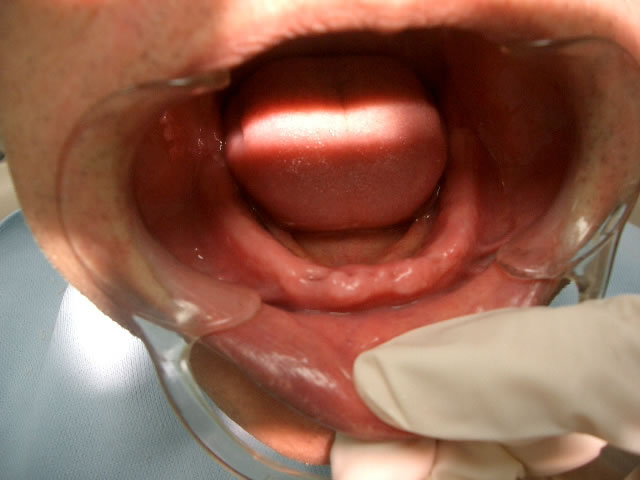

- 顎骨がほとんど無い状態

- が、ここまで骨がなくなると悲惨です。インプラントも出来ないでしょう。平成15年12月に東京で総義歯を専門にしている高名な3人の開業医の講演があったので参加しましたが、そんな高名な先生でさえ、このようなケースは触りたくないとおっしゃってました。